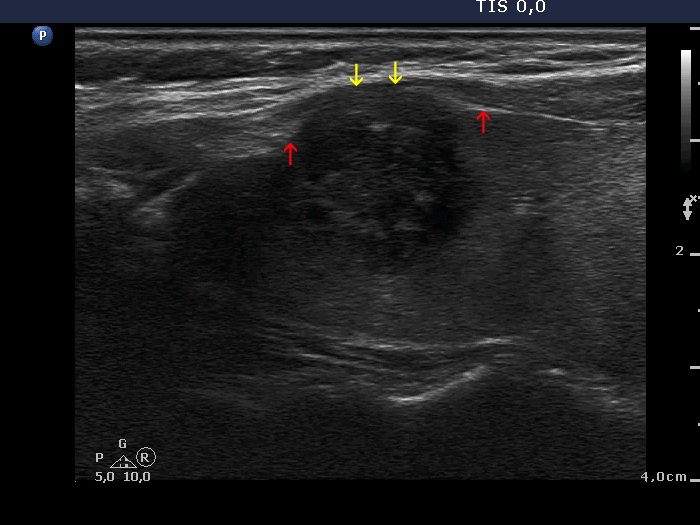

The borders of the nodule - case conp 060 (ultrasonographic picture 2b)

Right lobe, longitudinal view. This is a pathognomonic pattern of macroscopic extrathyroidal spread of a thyroid tumor. Such unequivocal example can be seen very rarely. It is worth noting the distance between the most ventral surface of the nodule (yellow arrows) and the most ventral surface of the lobe (red arrows).